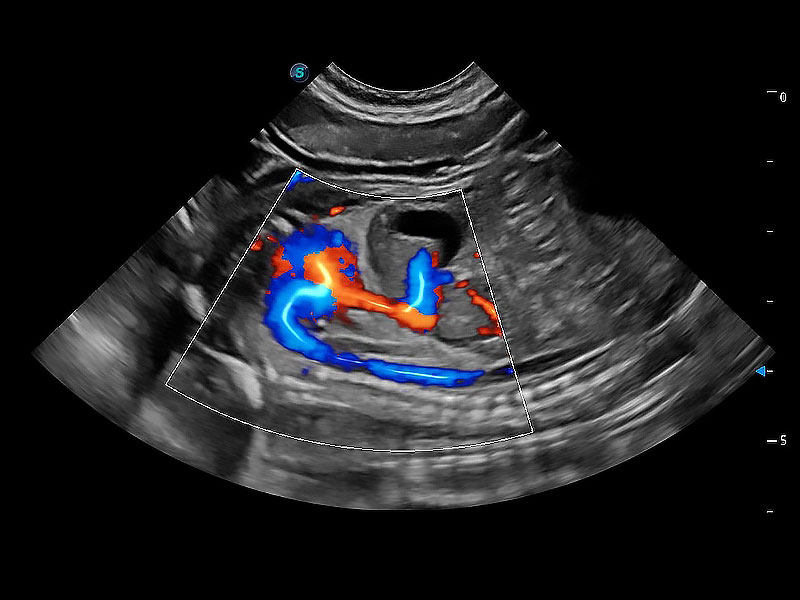

ProPet 80 配备了丰富的心脏探头群、先进的成像技术和专业的心脏测量工具,可帮助动物医生为不同体型和生理结构的动物提供心脏和心肌功能的全面评估。

通过360度任意调节3条M型取样线,在同一心动周期上观察心脏不同位置的运动曲线,得到准确的心功能测量数据,有效评估心肌运动及左心室功能。